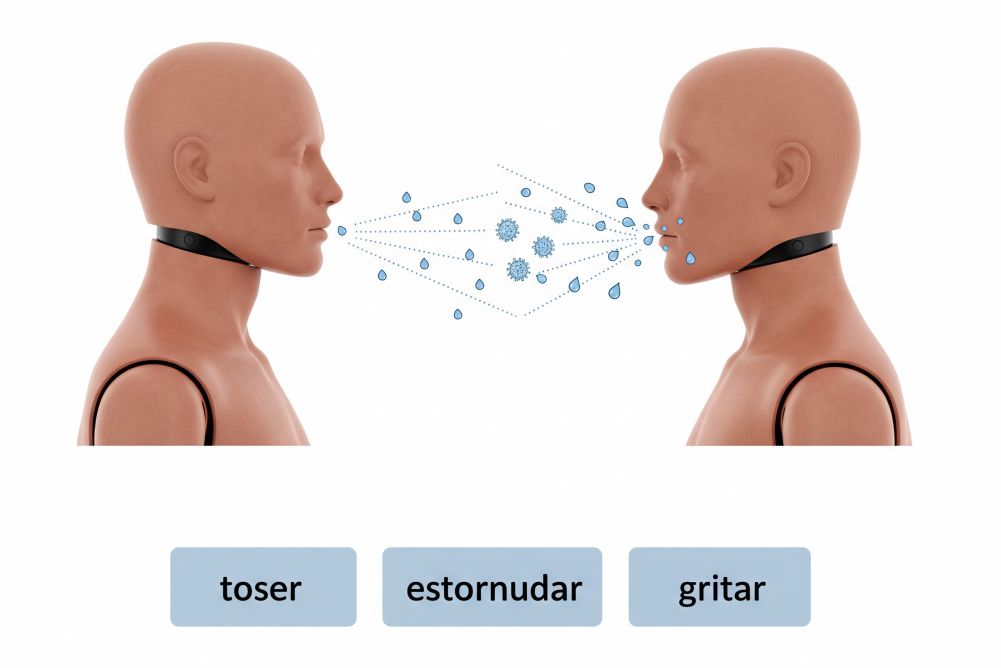

Exposición prolongadas de partículas de saliva

Se transmite por exposición prolongada a partículas (saliva) respiratorias de personas infectadas sin tratamiento, especialmente en contactos prolongados y cercanos.

No se contagia por:

No se transmite por contacto casual, relaciones sexuales, compartir ropa, dormir en la misma cama, compartir utensilios de cocina, por abrazos besos sencillamente es una enfermedad de baja contagiosidad